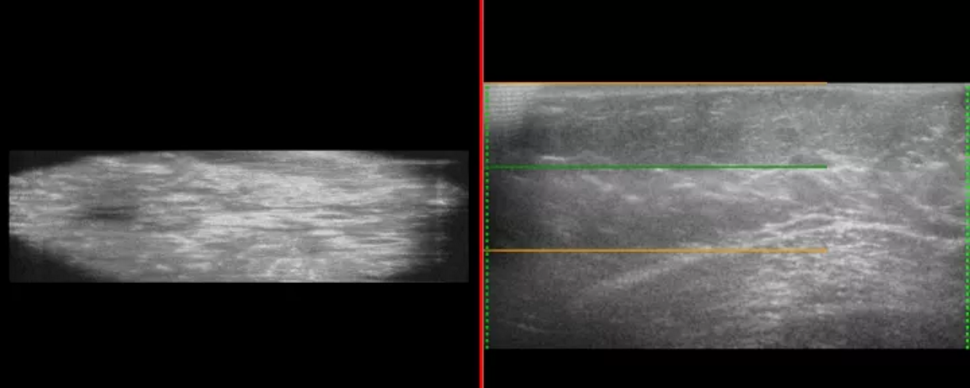

3. 3D超声

基于与多家国内外最一流的医院的合作,以超大量的乳腺癌3D超声样本数据为基础,我们开发了“清风3D超声智能诊断系统”。

待3D超声智能诊断软件测试通过后,将其加载在超声设备里,使3D超声设备在扫描检测时能自动分析出乳腺癌的诊断情况,进而开发出一体化3D超声智能诊断设备。3D超声乳腺癌自动诊断软件系统及3D超声智能设备将为患者提供提供乳腺癌早期、便捷、无创伤的筛查检测系统,以提高人民群众的检测覆盖率和癌症早期筛查的检出率。